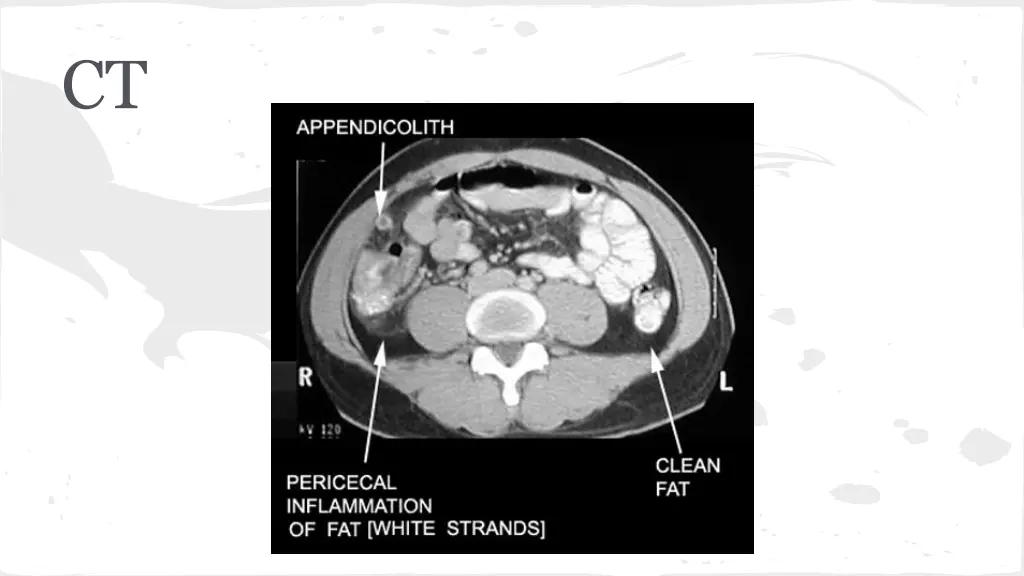

Appendicitis Symptoms Right lower quadrant pain/Periumbilical Pain Loss of appetite Vomiting Exam RLQ tenderness Fever +/- rebound

Appendicitis Test of Choice Management Surgery Consult NPO Fluids Morphine Abx